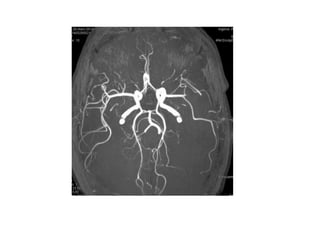

• 29 ans

• Infarctus sylvien gauche étendu

• De cause cardioembolique

• Présence d’un mismatch Diffusion/FLAIR

MAIS

• Anticoagulation efficace en cours:

• lovenox 0.6 mg 2 fois/jour

• Previscan (dernier INR le matin à 1.02)

• Plavix

• Kardegic

Bilan hémostase

• INR 1.62 (< 1.70 mais augmentation rapide par

rapport au dernier prélèvement il y a moins de 24 heures

et traitement administré quelques heures avant la

survenue de l’infarctus)

• TCA 1.23 (inférieur à l’objectif requis mais élevé)

• Après entretien et information de la famille

• Thrombolyse intraveineuse avec administration

de 63 mg rtPA correspondant à 70 kg (poids réel

100 kg)

• NIHSS post-thrombolyse 16: amélioration du

déficit moteur mais persistance d’une aphasie

sévère

• J2 – NIHSS à 9

• J 3 – NIHSS à 7 – reprise de la marche

• J7 – NIHSS à 3